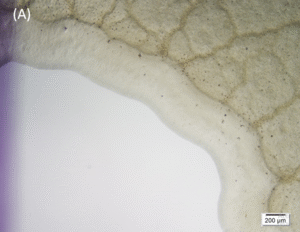

Microscopic images (4× objective, 5× magnification, Olympus cellSens Standard software) of the central area inoculated with Pseudomonas aeruginosa and treated with UV-C for 15 seconds (A) and the control area (B). A clear demarcation of the treated area can be seen on image (A).